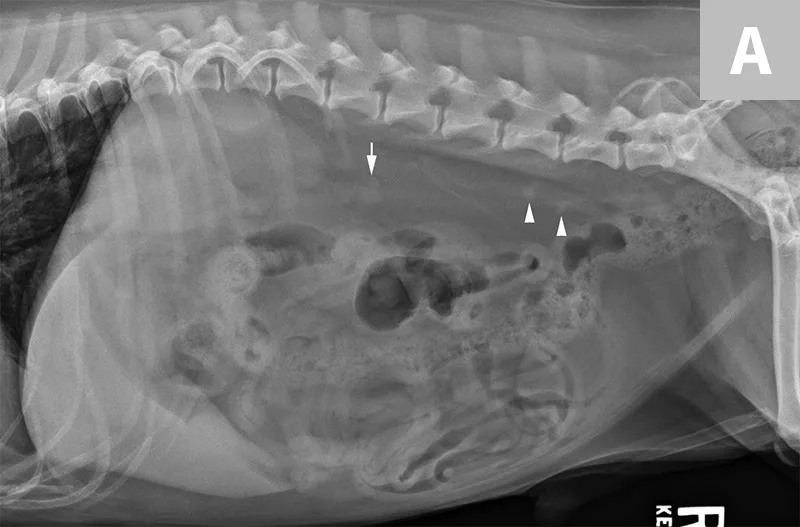

Lateral abdominal radiograph of a dog with 2 well-defined, oval mineral opacities superimposed over the retroperitoneal space caudal and dorsal to the kidneys (arrows). Based on the ventrodorsal projection (not shown), these calculi were likely to be associated with the right ureter.

Ureteral calculi are a common cause of ureteral obstruction; localization of ureteral calculi is imperative prior to choosing appropriate management. While ureteral calculi have been reported as the most common cause of ureteral obstructions, other causes such as iatrogenic ligation, blood clots, tumor, strictures (congenital and acquired), solidified blood stones, and a circumcaval ureter have been reported.4-7